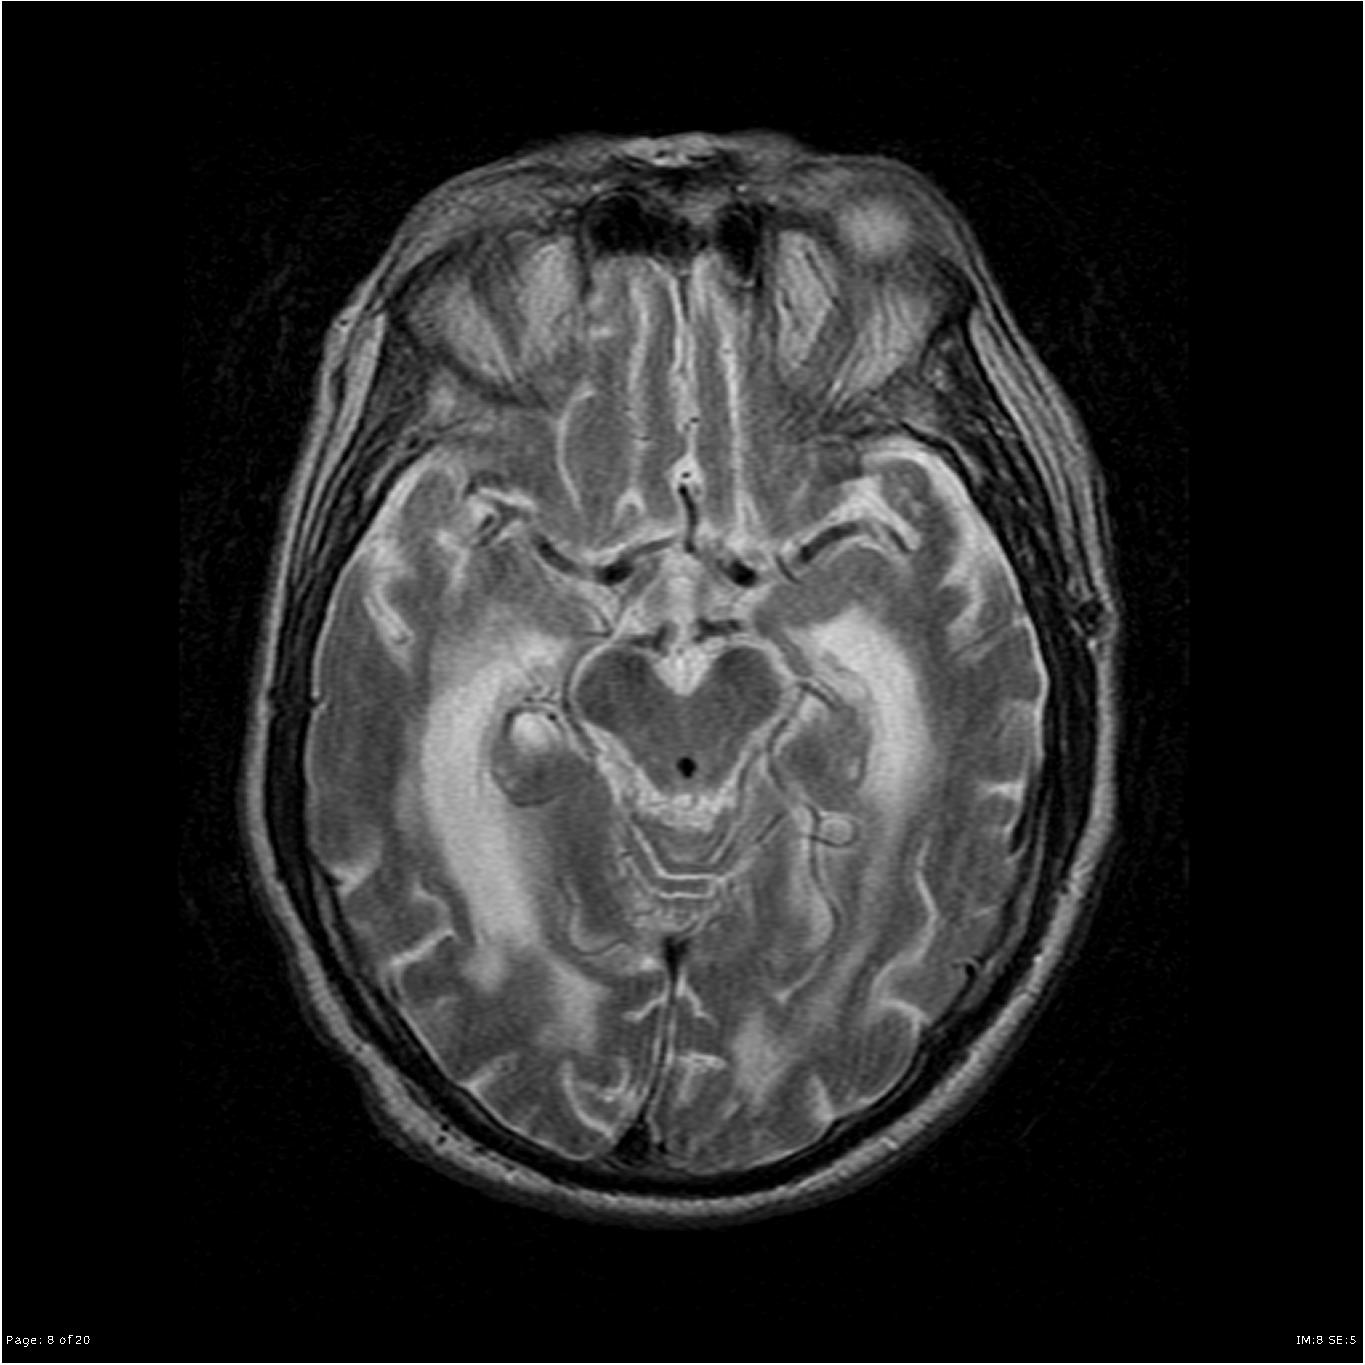

Hydrocephalus MRI – wikidoc

MRI of hydrocephalus – Stock Image – M170/0370 – Science Photo Library

File:Congenital hydrocephalus MRI02.jpg – Embryology

Hydrocephalus MRI – wikidoc